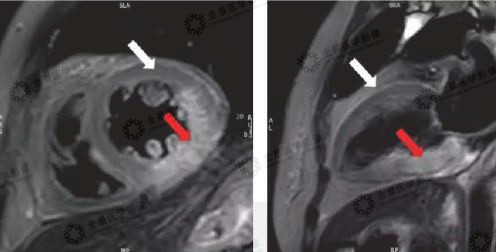

▲黑血序列:

白色箭头:正常心肌

红色箭头:水肿心肌